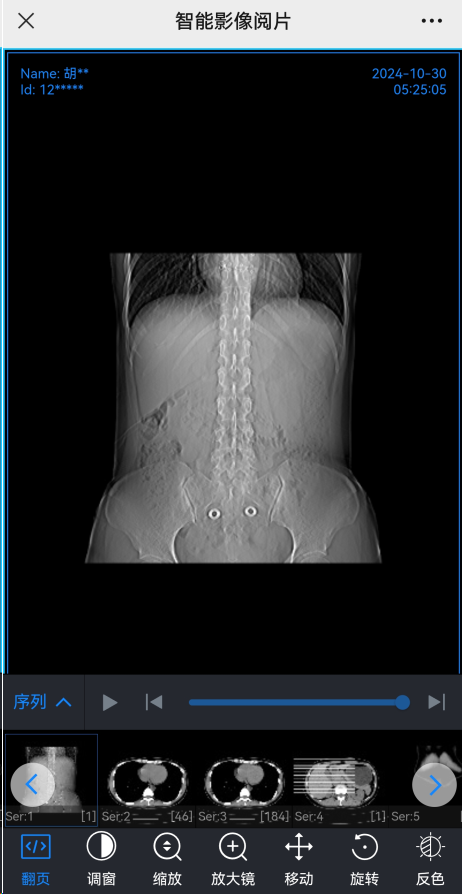

云胶片是基于移动互联网和云存储的新型的医学影像服务,是相对于传统塑料胶片的一种信息化升级,它由数字化的影像和报告取代传统的物理胶片和纸质报告,就相当于用数码手机取代胶片相机。通俗讲就是把胶片放在云端,只需在手机点一点,就能随时随地查看到胶片。

在完成检查后,在手机上点一点就可以查看自己的检查图像和报告。

可以查看检查原始DICOM文件。